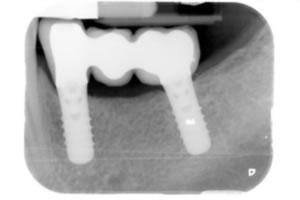

Radiograph of permanent bridge on implants.